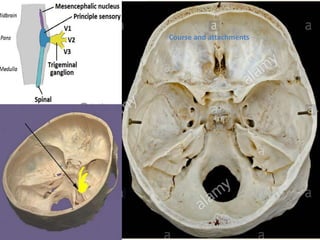

 Various nuclei associated with the fifth nerve are situated within the pons.

1. Main Sensory nucleus ( tactile sensation )

2. Mesencephalic nucleus ( proprioceptive sensibility )

3. Spinal tract nucleus ( pain and temperature)

4. Motor nucleus

ORIGIN

Course and attachments

MOTOR ROOT

 It arises separately from the sensory root originating in main nucleus in pons

 Its fibers travel anteriorly along with sensory fibers, but separately to the region of

trigeminal ganglion.

 At the semilunar ganglion it passes in a lateral and inferior direction under the ganglion

towards foramen ovale, through which it leaves the middle cranial fossa along with the

sensory root of mandibular nerve.

 After it exits the skull, it unites with the sensory root of mandibular nerve and forms a

single nerve trunk.